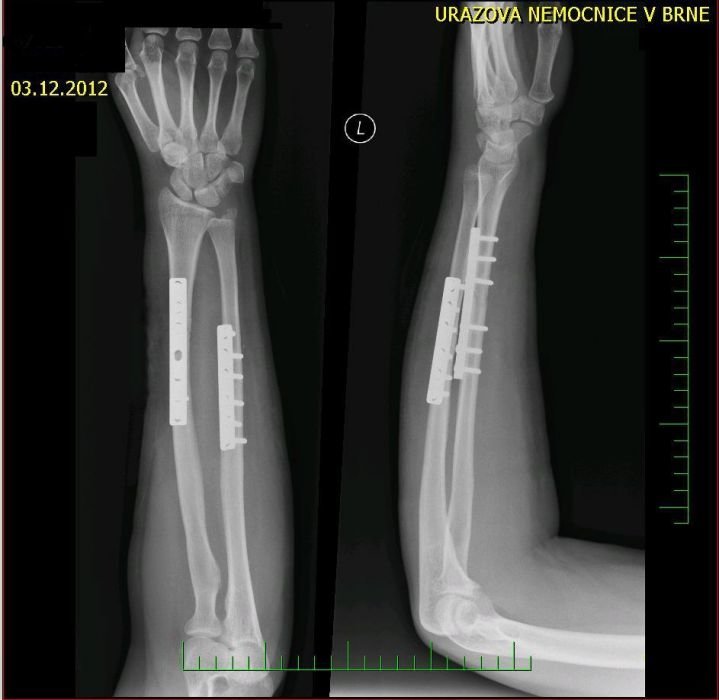

Nemá smysl se přetlačovat se stromem :)

Koukám, že v brněnské úrazovce to vrtal zručný řemeslník, žádnej vrut šejdrem, čistá práce. Tak ať se dobře zhojíš.